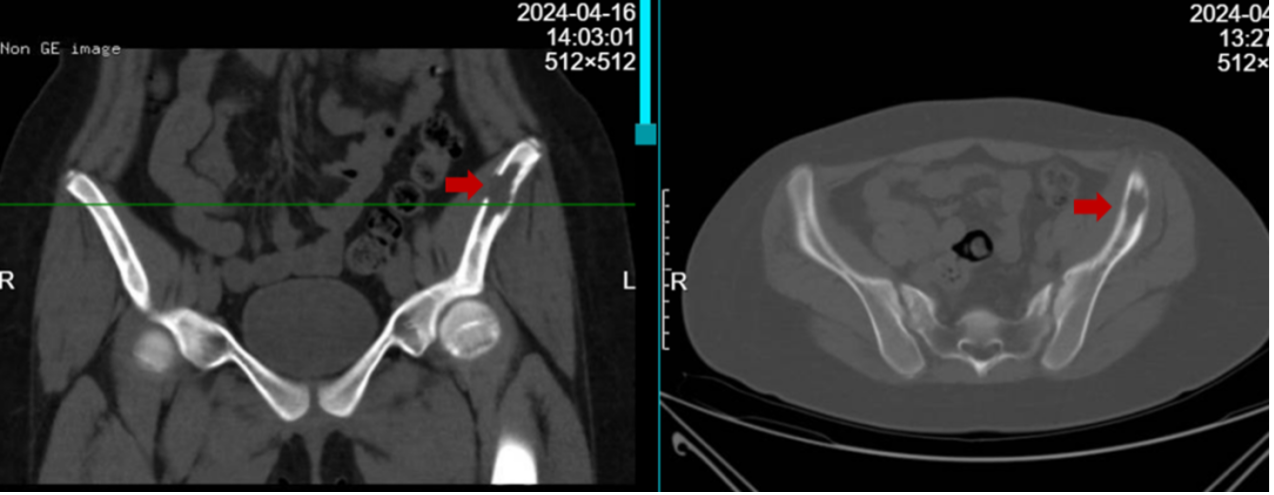

图:骨盆CT提示左侧髂骨翼溶骨性病变伴骨皮质破坏

图:骨盆核磁共振提示左侧髂骨翼病变伴周围软组织水肿